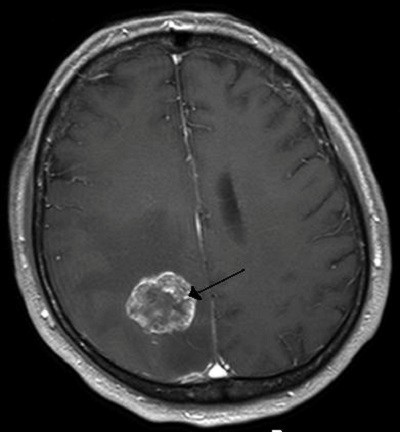

发生于颅腔内的神经系统肿瘤。

颅内肿瘤症状:头痛、呕吐、头晕与眩晕、癫痫、复视、精神及意识障碍

治疗:颅内肿瘤总治疗原则是以手术为主、辅以放射和化学药物治疗的综合治疗。目前来说,治疗方法以手术为主。可分为两大类:一类是肿瘤直接手术,包括肿瘤切除术、开放活检术;另一类是姑息性手术,包括内减亚术、外减压术、脑脊液分流术,目的仅为暂时降低颅内压,缓解病情。